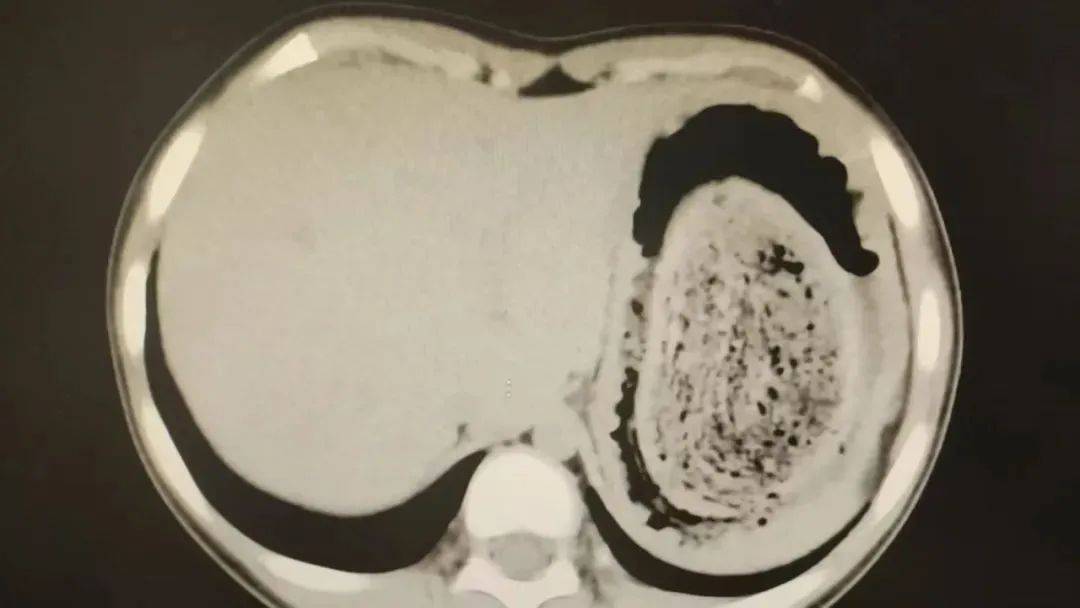

在胃镜帮助下,妮妮胃里的情况逐渐明了皇冠信用网登2。一个滚圆黑色的毛发球混合着食物残渣占据整个胃腔,这些头发相互缠绕形成一个实心的“发石”,此外胃里还有一个鸡蛋大小的溃疡。

症结找到了,就是这个巨大的发石导致妮妮出现营养不良、贫血和闭经,当务之急就是取出“发石”,给胃进行“大扫除”皇冠信用网登2。

“发石”混杂着食物残渣,就像一个黑色的小西瓜皇冠信用网登2。由于整个“发石”体积太大,为避免损伤胃壁,医生借助手术工具将“发石”切割、分解,再小心翼翼地分块取出。整场手术持续2个多小时,最终取出4斤头发碎片。